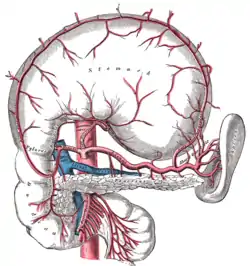

Tronco celíaco con sus ramas. (Lienal es un término antiguo para referirse a la arteria esplénica). El estómago está levantado e invertido. Compárese con la imagen anterior. | ||

Existen tres divisiones principales de la arteria celíaca (arterias: gástrica izquierda, esplénica y hepática común). A continuación se muestra la arteria celíaca con sus sucesivas ramas, las ramas de aquellas y sus respectivas anastomosis.[2]

Arteria hepática común

Se origina del tronco celiaco, se dirige hacia abajo, adelante y a la derecha por encima del páncreas, después de un trayecto de 4 cm. se divide en 2 ramas: la arteria gastroduodenal y la hepática propia. En su origen la arteria toma contacto con el borde superior del páncreas, cruza el pilar derecho del diafragma, luego se sitúa en el piso del vestíbulo de la transcavidad de los epiplones. En su trayecto de atrás hacia delante, levanta el peritoneo y forma el pliegue hepatopancreático. Posterior a esto la arteria hepática común se oculta tras la ampolla duodenal; se relaciona hacia arriba con el lóbulo caudado. Está rodeada por un plexo nervioso grueso emanado del plexo celiaco así como de vías linfáticas..tiene cuatro ramas colaterales:

- Pancreáticas. - Duodenales superiores. - Para los ganglios linfáticos escalonados. - Peritoneales y para el epiplón menor.

En sus ramas terminales se encuentra:

- Arteria gastroduodenal: se dirige hacia abajo y adelante, pasa en la porción superior del duodeno y de la cabeza del páncreas a la derecha del tubérculo omental. Delante de la cabeza del páncreas su origen marca la terminación de la arteria hepática común y el comienzo de la arteria hepática propia. Antes de ubicarse por debajo del duodeno la gastroduodenal proporciona la arteria pancreatoduodenal superior posterior. Se divide en dos ramas terminales:

A).- La arteria gastroepiploica derecha: se origina de la bifurcación de la arteria gastroduodenal que surge de la porción Terminal de la arteria hepática común, este origen se sitúa por debajo del borde inferior del duodeno en contacto con el páncreas, viaja inferior a la curvatura mayor del estómago y se anastomosa con la arteria gastroepiploica izquierda que viene de la arteria esplénica.

B).- La arteria pancreatoduodenal superior anterior.

- Arteria hepática propia: describe un codo cóncavo hacia arriba y hacia la izquierda que la sitúa en la raíz hepática, esta delante de la vena porta hepática, a la izquierda de la vía biliar principal, entre las dos hojas del epiplón menor. Es oblicua hacia arriba y a la derecha. Termina por la bifurcación en las arterias hepáticas izquierda y derecha. Sus ramas terminales son cuatro:

A).- Arteria gástrica derecha (pilórica): : originada de la arteria hepática propia, es oblicua hacia abajo y adelante, está situada en el epiplón menor el cual llega al borde superior del píloro en donde se divide en dos ramas terminales que siguen la curvatura menor. Ambas ascienden por esta al encuentro de las ramas correspondientes de la arteria gástrica izquierda. La acompañan vasos linfáticos y una vena supraepiploica, inconstante. La rama posterior de la arteria gástrica derecha se anastomosa con la rama posterior de la arteria gástrica izquierda, la anterior puede hacerlo o terminar en las ramas del estómago.

B).- Pequeñas ramas para la vía biliar principal. C.- La arteria cística, que se origina a menudo delante de la arteria hepática derecha. D.- Arterias para la cápsula fibrosa del hígado (red perihepática).

Sus ramas terminales penetran en el porta hepático, delante de la rama correspondiente de la vena porta hepática y se expande en el hígado, siguiendo las ramificaciones venosas. La rama más derecha es más voluminosa que la izquierda. Sus ramas arteriales son anatómicamente terminales.

Arteria esplénica

Se origina en el tronco celiaco frente a la 1.ª vértebra lumbar, por lo tanto, lejos del bazo. Después de un corte segmento suprapancreatico, oblicuo hacia abajo y a la izquierda, transcurre transversalmente, sigue el borde superior del páncreas, pasa por delante de la cola u por último llega al hilio del bazo, donde se divide en dos ramas terminales. En sus relaciones del segmento suprapancreático, esta arteria pertenece en ese momento a la región celiaca, esta arteria se encuentra hundida en el plexo celiaco y sus ramos. Está situada detrás del peritoneo parietal, detrás de la porción retrogastrica de la transcavidad de los epiplones que la separa de la parte media de la curvatura menor del estómago. En el segmento retropancreático es cóncava hacia tras como el propio páncreas. Este segmento de la arteria esplénica es muy sinuoso, la arteria aquí comparte sus relaciones con el cuerpo del páncreas: anterior con la cara posterior del estómago a través de la transcavidad de los epiplones, posterior con la raíz y la celda renal izquierda, por intermedio de la facia retropancreática y de la facia prerrenal. Las partes más inferiores se ubican por detrás del páncreas, debajo de esta arteria esta la vena esplácnica. En su segmento Terminal o hiliar, esta describe una curva cóncava al igual que la cola del páncreas. Esta pasa superior a la cola, la vena queda por debajo de la arteria y estos dos vasos llegan al ligamento pancreaticoesplénico en la parte posterior e izquierda de la transcavidad de los epiplones, detrás del estómago y del hilio del bazo.

En sus ramas colaterales se distinguen:

- Ramas pancreáticas destinadas al cuerpo y a la cola, así como la arteria pancreática dorsal. - Rama gástrica, arteria gástrica posterior: de dirección ascendente, irriga la cara posterior del fondo gástrico, el cardias y la cara posterior del esófago abdominal. - Arteria de la extremidad superior: se origina antes que la arteria llegue al hilio, da de dos a tres ramas al fondo gástrico y llega hasta la extremidad superior del bazo.

Da dos ramas terminales que son la superior y la inferior, la superior se dirige hacia la parte alta del hilio donde da de cuatro a seis ramas, la posterior se dirige al tercio inferior de hilio, esta es la que da lugar a las arterias gástricas cortas y a la arteria epiploica izquierda.